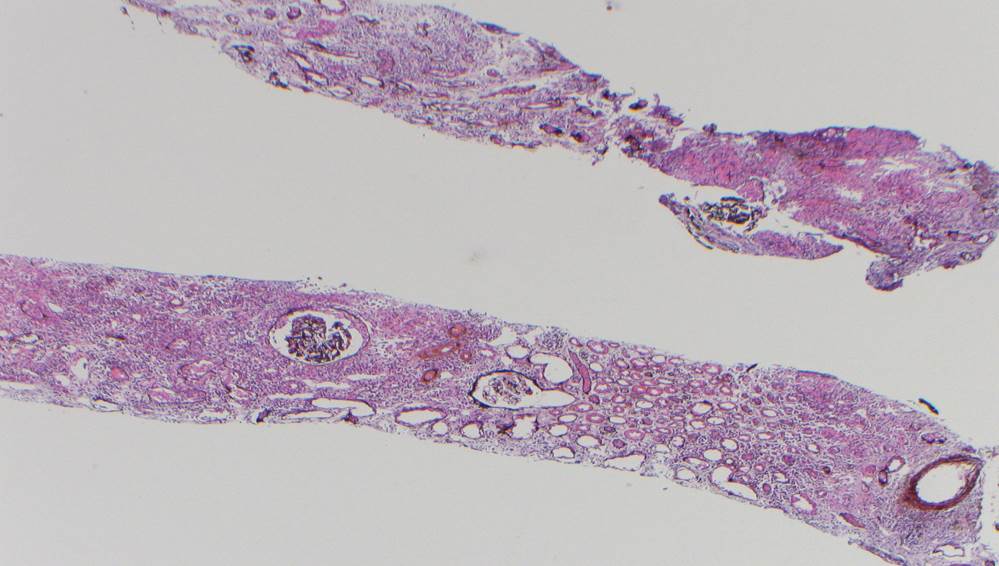

A renal allograft biopsy is essential to differentiate adenoviral nephritis from that of acute rejection or other pathology. Typical light microscopic findings in adenovirus nephropathy include tubular cell necrosis (with tubular basement membrane rupture) associated with severe interstitial inflammation (sometimes with granuloma formation), focal interstitial hemorrhage and viral cytopathic changes including peripheral condensed chromatin, basophilic nuclear inclusions and nuclear enlargement. In some cases such as ours, viral inclusions are not identified, presumably because of the focal nature of viral infection in the kidney. Immunoperoxidase staining can be used to confirm the presence of adenovirus within the nuclei, and to a lesser degree, within the cytoplasm of tubular epithelial cells; although weak, our case showed positive staining. These viral particles are visible under electron microscopy, measuring approximately 75 nm, however they were absent in our patient. Diagnosis in such cases can be clinched by urine examination showing white cell casts and decoy cells, and PCR on the urine testing positive for viral DNA.